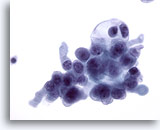

Figure 72

Lymph node FNA, malignant lymphoma.

This specimen is cellular with all cells scattered throughout the photo. Compare a small mature lymphocyte with the vast majority of the rest of the cells that are slightly enlarged. 20x

Lymph node FNA, malignant lymphoma.

This specimen is cellular with all cells scattered throughout the photo. Compare a small mature lymphocyte with the vast majority of the rest of the cells that are slightly enlarged.

20x